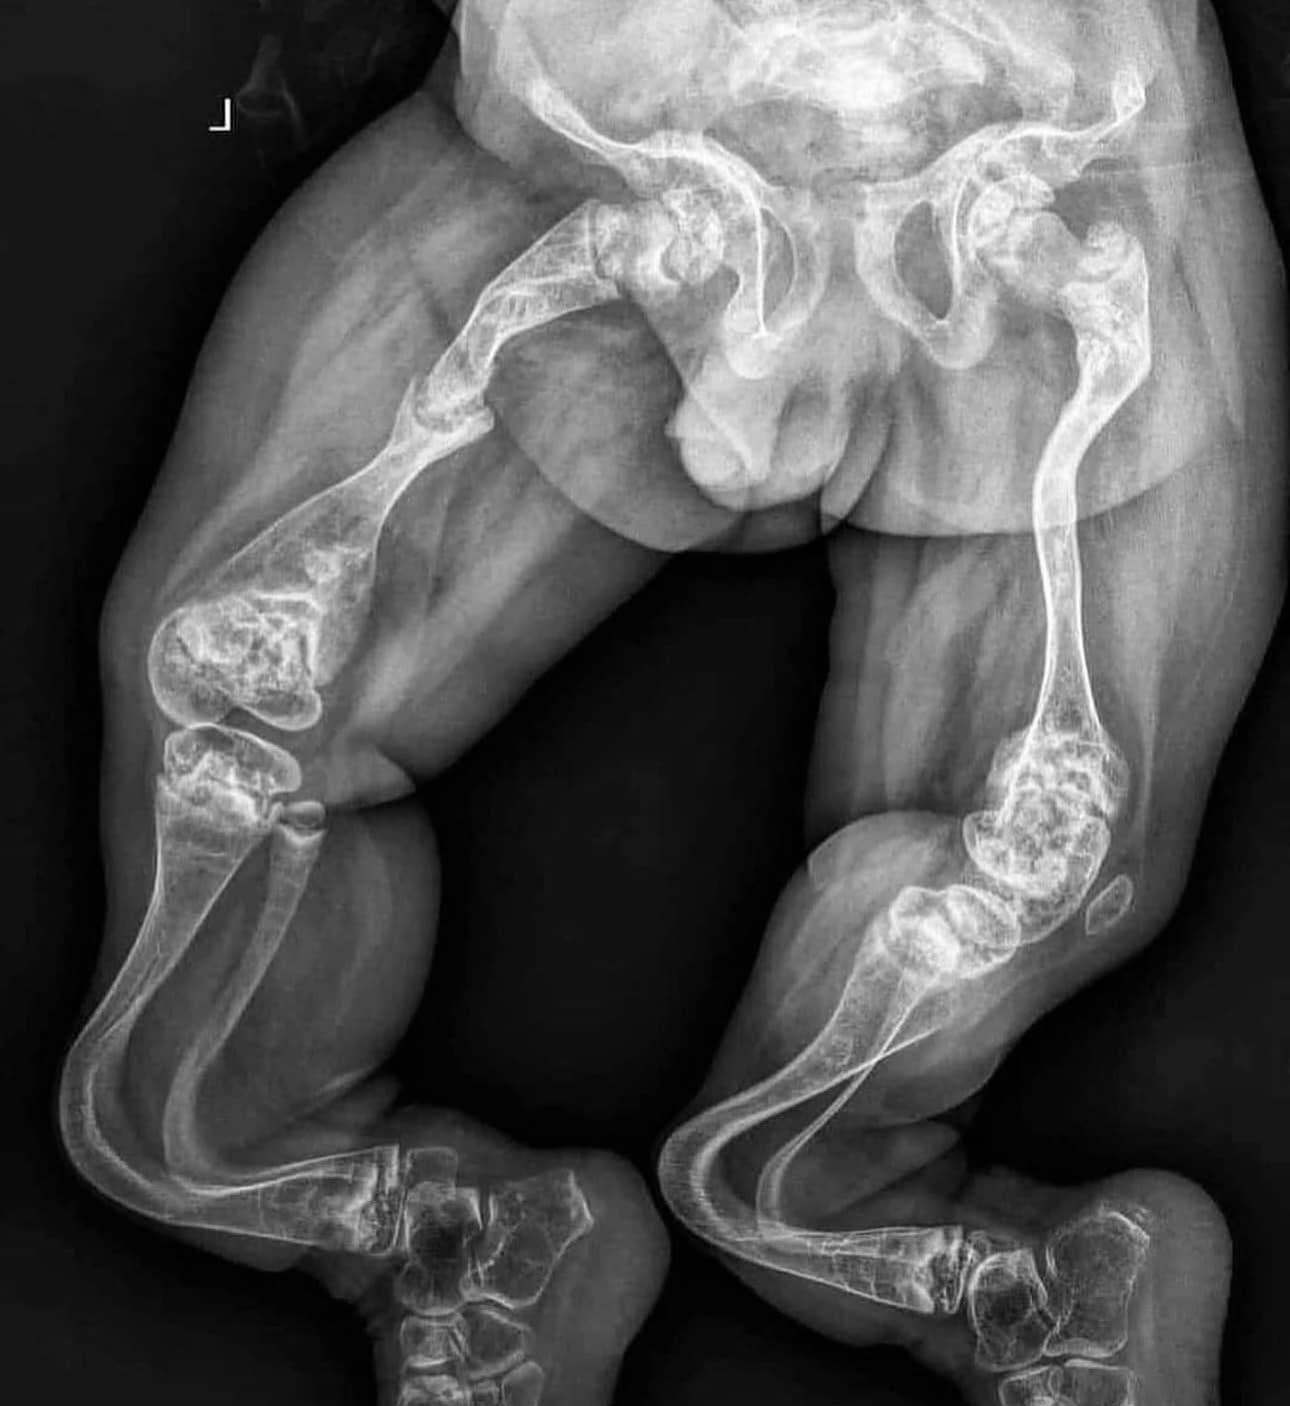

Coxa vara включає всі форми зменшення кута шийки та діафіза стегнової кістки менш як 120-135°. Аномальний розвиток проксимального хрящового діафізу стегнової кістки та дефектна осифікація прилеглого метафіза є відповідальними за прогресуюче зменшення кута шийки та діафрагми. У важких випадках також може бути виявлений окремий трикутний фрагмент, що залучає нижньо-медіальну частину шийки стегнової кістки.

Ці анатомічні та біологічні фактори, що лежать в основі характеристик біомеханічного навантаження варусного стегна, призводять до прогресуючого нахилу проксимальної епіфізарної пластинки з укороченням шийки стегнової кістки та супутнім відносним розростанням вертлюга. Часто виникає серйозна деформація стегна, як клінічно, так і рентгенологічно, перебіг якої не завжди ясний, а лікування не завжди успішне.

Вроджена варусна кишка (CCV) рентгенологічно диференціюється від інших форм варусної хвороби проксимального відділу стегнової кістки за характерною ознакою перевернутого Y-подібного просвіту (див. зображення нижче). Цей просвіт складається з проксимальної фізарної пластинки та фрагмента кістки нижньо-латерально від фізису, який представляє обмежену область аномальної кальцифікації.

Інші, більш загальні рентгенологічні ознаки спільні з іншими причинами coxa vara. Серед них:

- Зменшення кута шийки та діафрагми, часто наближається до 90° або менше

- Менша і плоска голівка стегнової кістки

- Більш вертикальна орієнтація фізарної пластинки

- Зменшення анверсії стегнової кістки або навіть ретроверсія головки на шийці стегнової кістки

- Coxa brevis

- Часто неглибока кульшова западина більш овальної форми

Уважно перевірте плівки на наявність доказів набутих або метаболічних причин coxa vara, таких як аваскулярний некроз, зсув головного епіфіза стегнової кістки (SCFE), септична деструкція головного епіфіза або метафіза стегнової кістки, фіброзна дисплазія та рахіт.

У дослідженні, яке запропонувало кількісну оцінку CCV за допомогою епіфізарного кута Гільгенрейнера (HEA), Weinstein та ін. також припустили, що замість використання лінії Гільгенрейнера, яка може змінюватися з нахилом тазу, спричиненим зазвичай пов’язаною невідповідністю довжини кінцівок, горизонтальна лінія, паралельна замість цього можна намалювати землю. Значення для стегон, уражених CCV, в середньому становлять 40-70°, але можуть досягати 70-90°. Цей фізичний кут залишається найбільш часто використовуваним засобом для кількісної оцінки вертикального нахилу проксимального відділу стегнової кістки при поданні та під час спостереження, а також для оцінки обсягу корекції, досягнутої хірургічним втручанням.